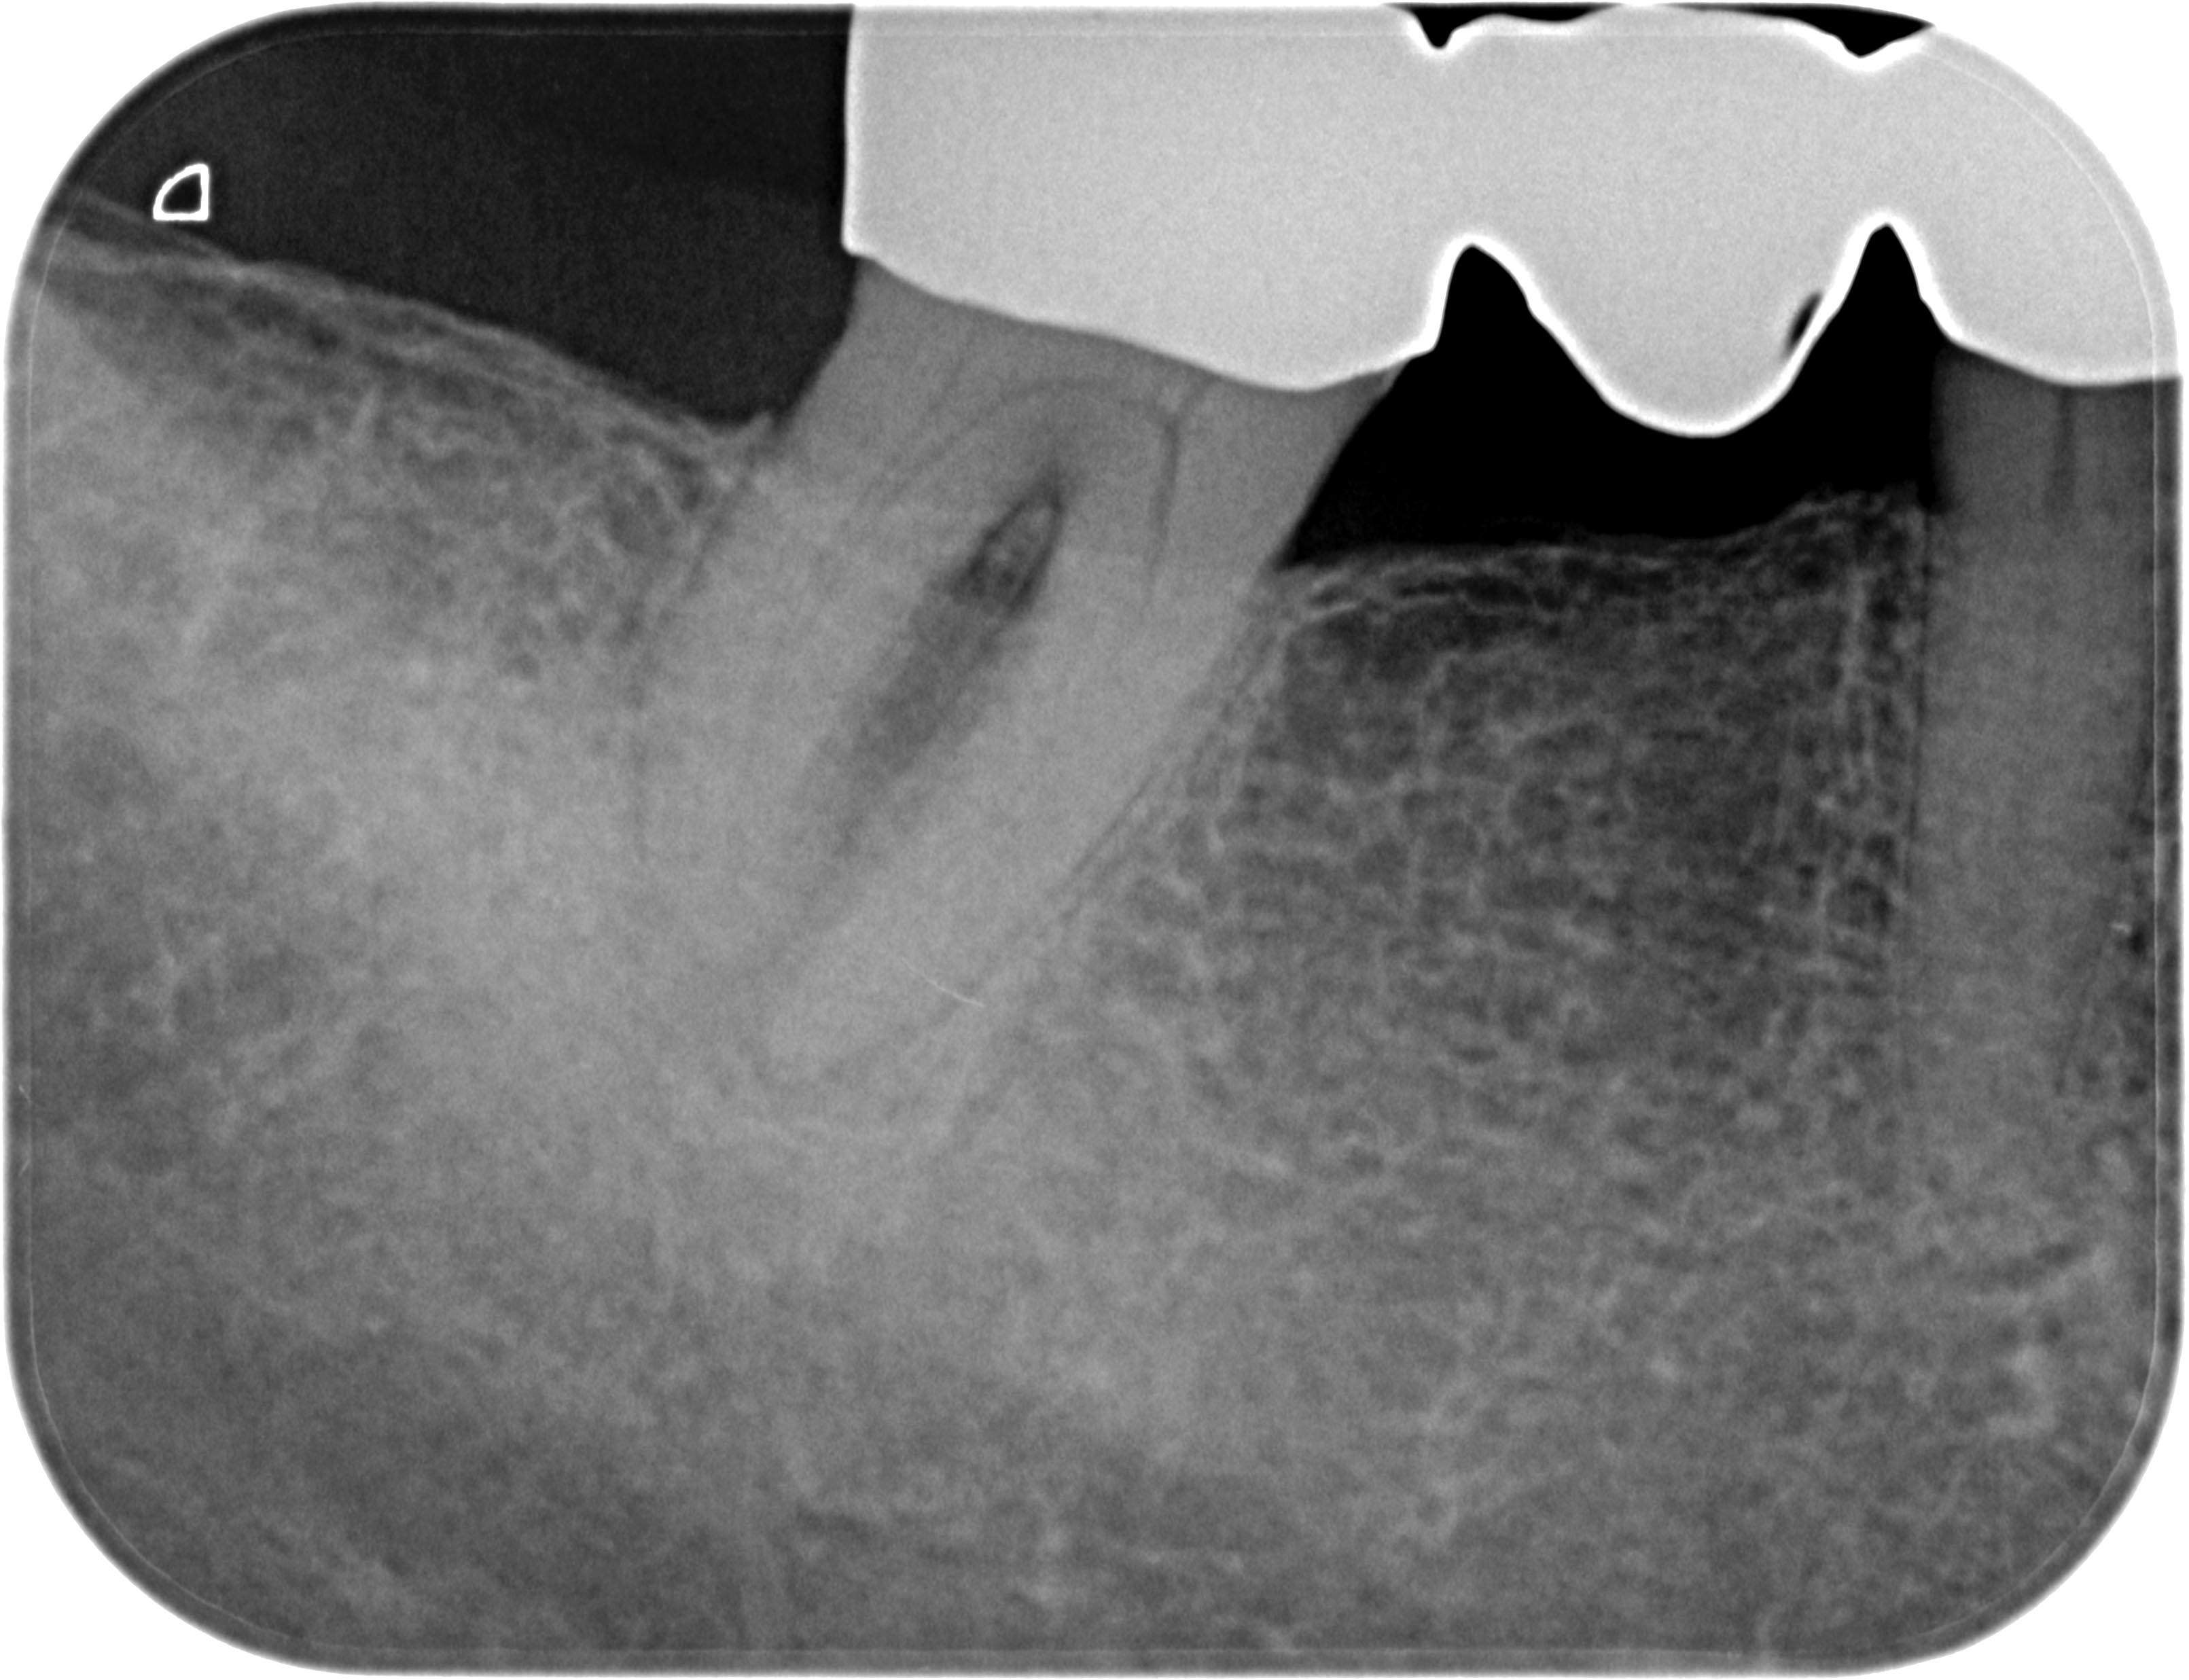

Resorption-1-6 Veröffentlicht 10. Juni 2013 am 3222 × 2473 in Was zeigt das DVT (4) ? Die Fälle Zahn 48, 45